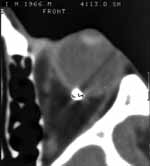

Для диагностики сквозных ранений глазного яблока (15 больных) использовали компьютерный томограф фирмы “Philips Tomoscan AV“. Основные технические характеристики: матрица 512х512, толщина среза 2–3 мм, время сканирования 1–2 с, количество срезов 10–15. Сканирование проводили в аксиальной или фронтальной плоскости. Применение мультипланарных реконструкций позволило определить точную локализацию инородного тела по отношению к структурам орбиты, его взаимоотношение с оболочками глазного яблока (Рис. 2).

[Увеличить]

Рис. 2. Применение мультипланарных реконструкций позволяет определить точную локализацию инородного тела по отношению к структурам орбиты, его взаимоотношение с оболочками глазного яблока.